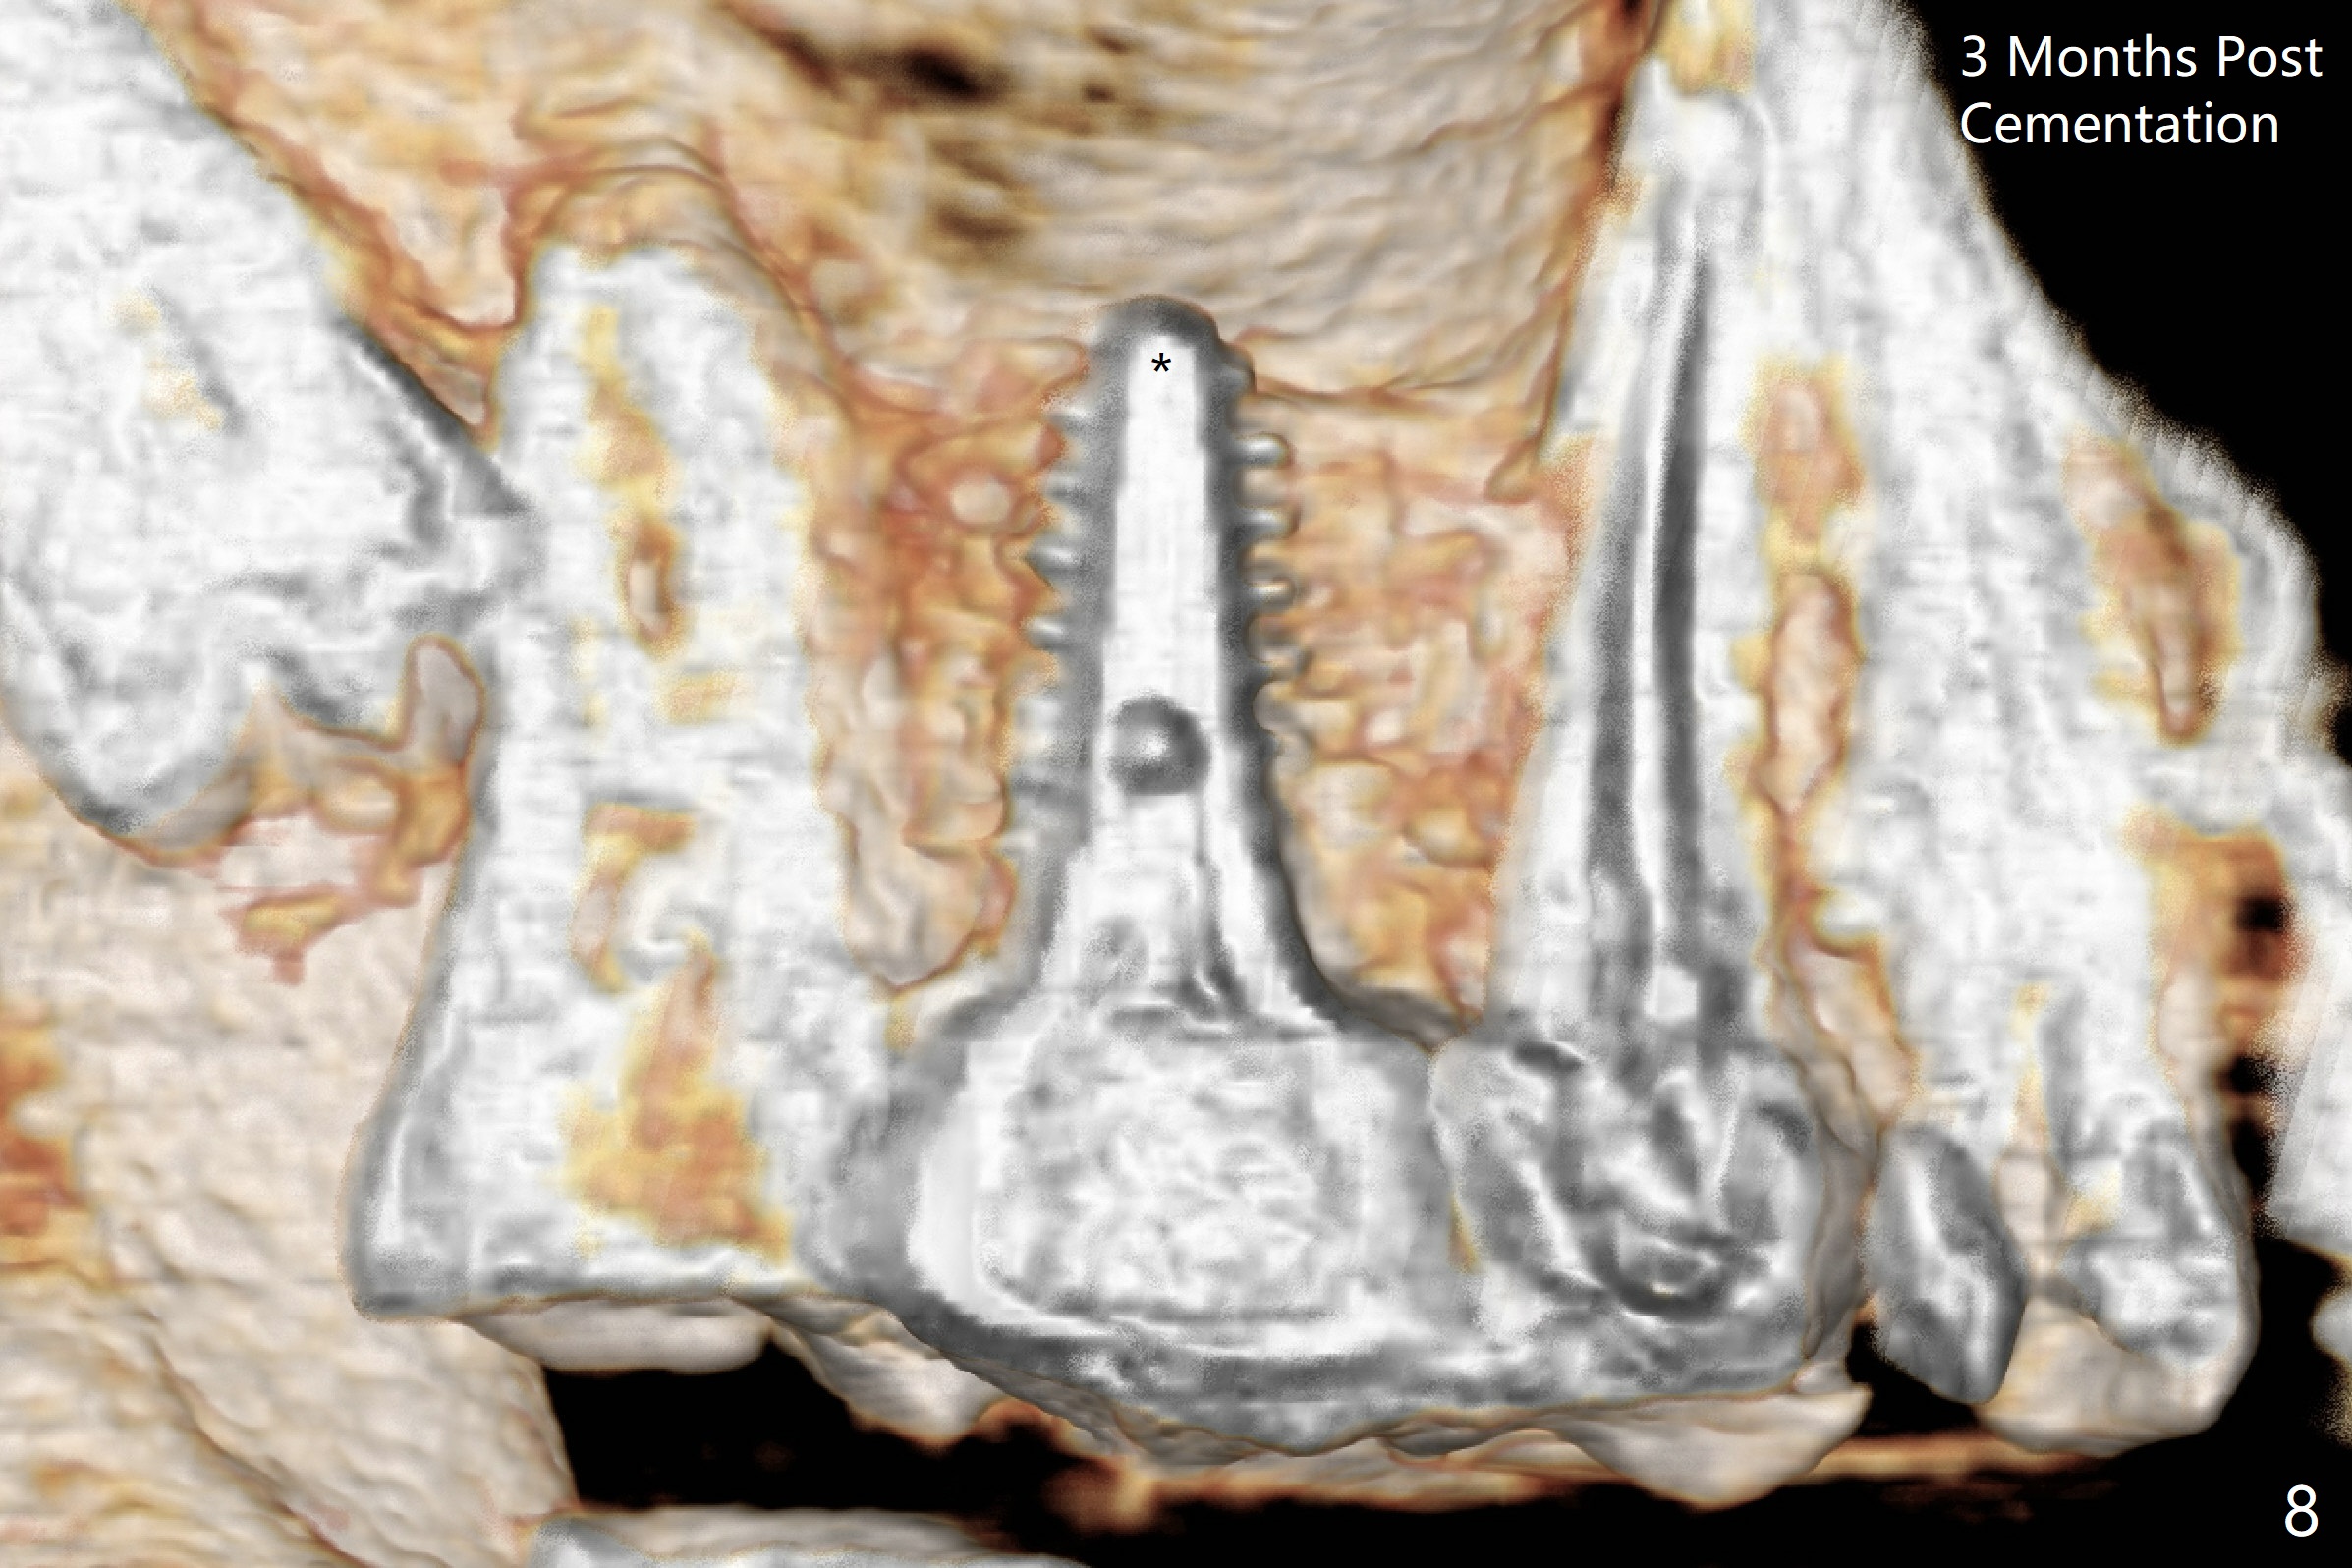

The ridge is wide at #14 11 months post socket preservation. Access and bone expansion (BEB) starts with Magic Split, followed by Magic Expanders 3.0, 3.8 and 4.3 mm from 8 to 9 mm for sinus lift. No bone is removed for osteotomy. Instead bone condensation occurs. After placement of a 4.5x11 mm dummy FC implant (Fig.1 with sinus lift (without bone graft)), a 5x9(2) mm Magicore (2 mm cuff) is placed with >55 Ncm with cuff margin at the gingival margin (Fig.2); a 5.5x3 mm solid abutment tries in. There is no occlusal clearance; trimming of the solid abutment will be needed. Later a healing screw is placed (Fig.3 *). There is no bone loss 5.5 months postop (Fig.4). A healing cap is placed without much tissue blanching. Instead a 5.5x3 mm solid abutment is placed; after height adjustment, impression is taken. A permanent crown is temporarily cemented 6 months postop (to rule out food impaction) and permanently re-cemented 7 months postop (Fig.5,6). CBCT taken 3-4 months post cementation shows that the implant threads are within the bone (Fig.7) and that the implant barely enters the sinus (Fig.8 *). That is significant since the patient has chronic sinusitis with thickened sinus membrane (Fig.9 *). The tooth #18 seems to have crazing line 10 months post cementation of the crown at #14 (overloading, Fig.10).